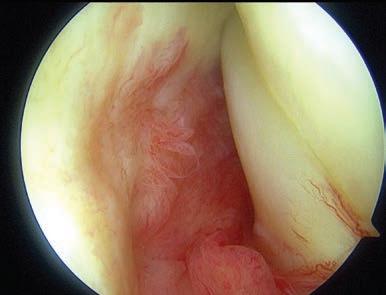

Dr Babak Shakeri joined the clinic earlier this year and recently introduced Office Gynaecology as a new service. Providing convenient treatment where women can be seen, assessed and treated quickly (often in a single visit or within one to two weeks), this service reduces the anxiety of long wait times and allows patients to get back to normal life, fast.

Diagnostic and operative hysteroscopy

NovaSure® endometrial ablation for heavy menstrual bleeding

MyoSure® procedures for fibroids and polyps

Colposcopy, cervical biopsy, and LLETZ for abnormal screening results

Contraception counselling and insertion of long-acting reversible contraceptives

Pelvic pain and endometriosis management in selected cases

Fertility-preserving gynaecology that integrates closely with IVF treatment.

Office gynaecology, sometimes called ambulatory or procedural gynaecology, refers to procedures that are performed in a clinic instead of a hospital.

For complex and high-risk cases, inpatient surgery is essential,

however many other lower risk common procedures are considered safe and effective in an outpatient setting. Evidence also shows that outcomes are comparable, and, in many cases, patient satisfaction is higher.

“My patients benefit from a quick diagnosis and treatment, for example, a woman with heavy bleeding can have a consultation, a hysteroscopy, and even a treatment such as polyp removal or ablation within one to two weeks. Similarly, a woman with an abnormal cervical screening test can have a colposcopy and if required LLETZ within the same timeframe.”

Pain management is critical to making outpatient gynaecology successful. Depending on the patient and the procedure, there are a range of options used for pain management, this includes oral analgesics and anxiolytics, local anaesthetic gel and targeted local anaesthetic injections, methoxyflurane commonly known as the “green whistle” and for selected cases – light or deeper sedation.

With Dr Shakeri, Concept now offers a complete suite of outpatient gynaecology services where everything is coordinated by a single team, offering patients seamless continuity of care.